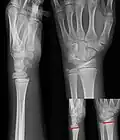

Изображения эпифизеолиза